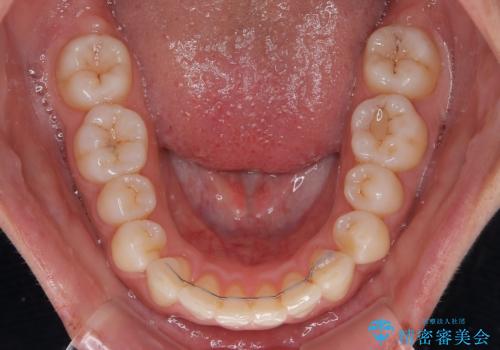

- 上下前歯が非接触となり、前方に突出していることを気にして来院された患者様です。

咬合力が強く、全体的に歯がすり減っているため、インビザライン単独での上顎歯列移動は困難と判断し、補助装置により上顎歯列を後方移動させ、その後インビザラインにて仕上げていくこととしました。

補助装置なしでも改善できる可能性はありましたが、補助装置で確実性を上げ、短期間できっちりと仕上げることができました。